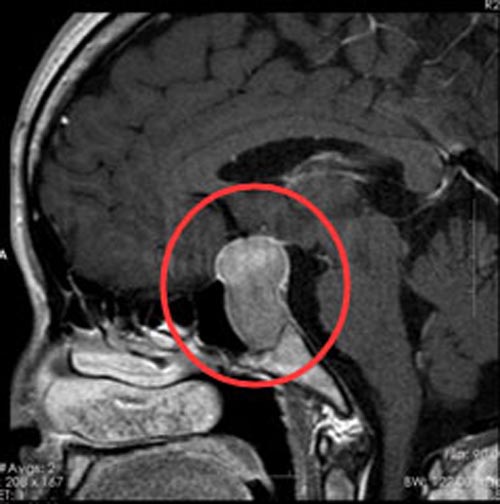

排除手术禁忌后,在内镜下行“经鼻蝶鞍区垂体瘤切除术+颅底重建术”,导航定位,全层切开硬脑膜,可见灰白色肿瘤流出,大小约3cm×2.6cm×0.7cm,囊肿组织,质软,易刮出,术程顺利。术后病理结果:垂体瘤。

▲手术前